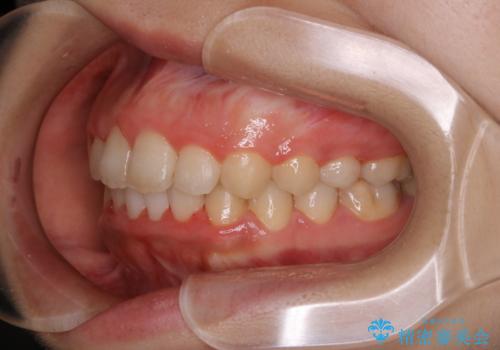

- 20代女性

- ワイヤー審美装置

- 7ヶ月

- 4年ほど前から地元の歯科医院にてインビザライン治療を行っていたが、引っ越し後に通いづらくなってしまったため、治療が途中で止まってしまっているとの事で来院されました。性格的にインビザラインの継続した使用が難しいとのことで、ワイヤー装置にて最終仕上げを行いました。

インビザラインは20時間以上の装着を厳守して頂くことで治療効果が期待できる治療となります。固定式のワイヤー装置に切り替えることで短期間で歯並びを整えることができ、大変喜んでいただけました。